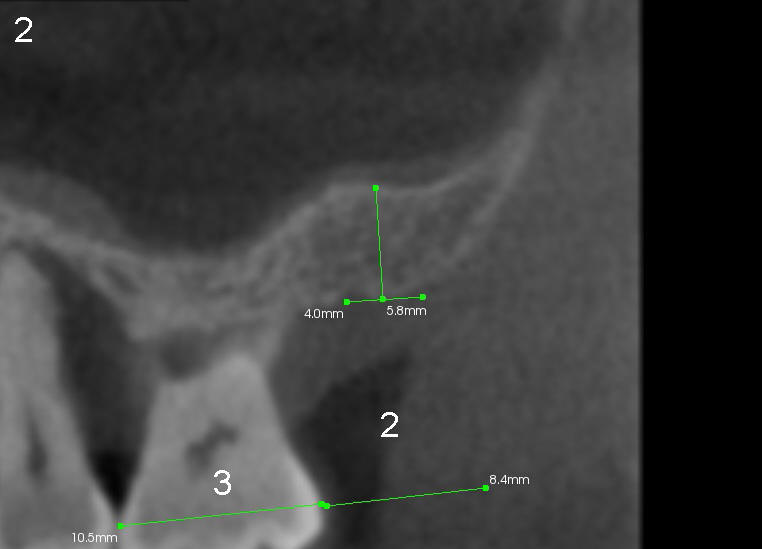

Calvin (at his 40s) has periodontitis and most likely bruxism. The tooth #2 has been lost for a while (Fig.1) with limited bone height (Fig.2 CT sagittal section, < 6mm).

Fig.7,8 are CT coronal sections, showing #2 ridge morphology and implant design, respectively.